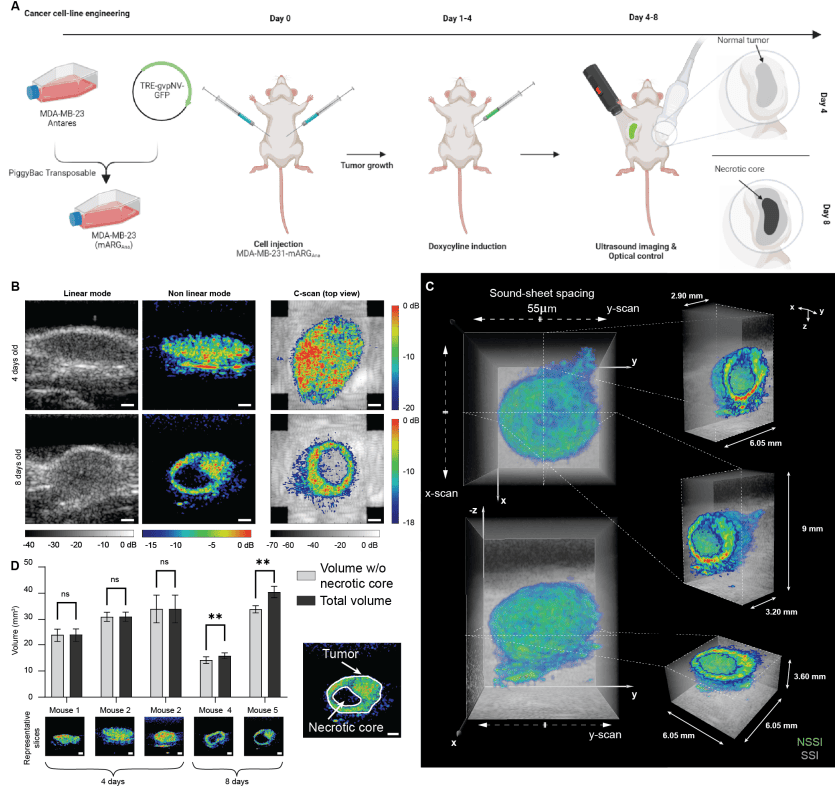

Также была исследована способность NSSM визуализировать ARG млекопитающих (mARG) в мышиной модели рака. Ортотопические опухоли были вызваны билатерально в жировых отложениях молочной железы самок мышей с ослабленным иммунитетом путем инъекции раковых клеток, сконструированных для создания нелинейно рассеивающих GV (3A). Экспрессия mARG in vivo была вызвана инъекциями доксициклина каждый день до 4-го или 8-го дня. Опухоли были визуализированы на 4-й день после индукции у 3 мышей и на 8-й день после индукции у 2 мышей.

В то время как SSM визуализация выявила анатомические структуры, включая опухолевые массы, NSSM успешно выявил пространственные паттерны экспрессии mARG в этих опухолевых массах (3B). На 8-й день после индукции NSSM выявил некротическое ядро опухолей молочной железы через отсутствие экспрессии генов. Высокая специфичность NSSM, которая устойчива к артефактам нелинейного распространения волн, была ключевой для этого экспериментального наблюдения. Объемная визуализация позволила отобразить поперечные сечения экспрессии mARG в плоскости XY, называемые C-сканированием (правая колонка на 3B). Опухоли были четко обнаружены на обеих стадиях, но некротические ядра были видны только на 8-й день после индукции.

Объемный NSSM, объединенный с анатомической SSM визуализацией, представлен на 3C. Общий сканированный объем простирается на 8.8 х 8.8 х 9 мм2 и был получен с шагом сканирования 55 мкм вдоль каждого массива RCA-преобразователя. На 3C показаны поперечные сечения экспрессии генов в плоскостях XZ, YZ и XY, иллюстрирующие возможности трехмерной навигации NSSM. Количественная оценка объемов опухолевых и некротических ядер была выполнена с помощью автоматического конвейера сегментации (3D). На 4-й день после индукции объемы, измеренные с некротическими ядрами и без них, были схожи, тогда как на 8-й день после индукции объемы, измеренные с некротическими ядрами и без них, показали статистически значимую разницу. Представительная автоматическая сегментация контуров экспрессии генов опухоли представлена на 3D. В этом примере визуализации глубоких тканей, учитывая статическую природу экспрессии генов при использованной скорости визуализации, 2D NSSM работал со скоростью 930 кадров/с, тогда как ортогонально сканированный объемный NSSM работал со скоростью 4 объема/с. Однако в теории 3D NSSM может достигать 94 объемов/с для этого набора параметров визуализации. Интересно, что количественная оценка объемов опухолей in vivo была бы невозможна на основе только анатомической ультразвуковой визуализации, что подчеркивает потенциал этого метода визуализации.